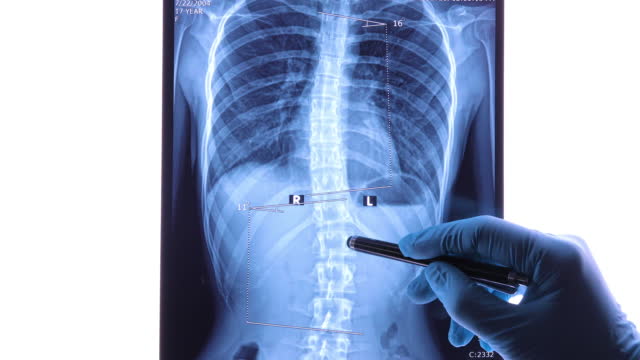

척추측만증은 척추의 공간 침범으로 인해 발생하는 질병으로, 이로 인해 척추의 굽힘이나 비틀림이 발생할 수 있습니다.